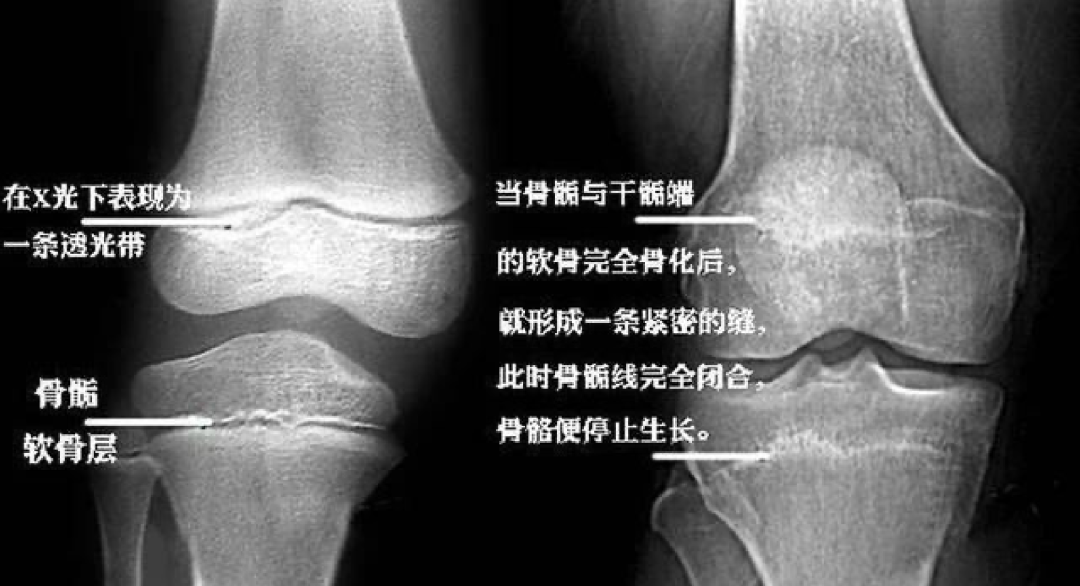

骨龄可真实地评价儿童的生物年龄,客观地评价儿童身高生长水平是准确评价孩子发育状况的“金钥匙”。开学前,来了解一下你孩子的生长发育,让你的孩子在学校快乐长高!